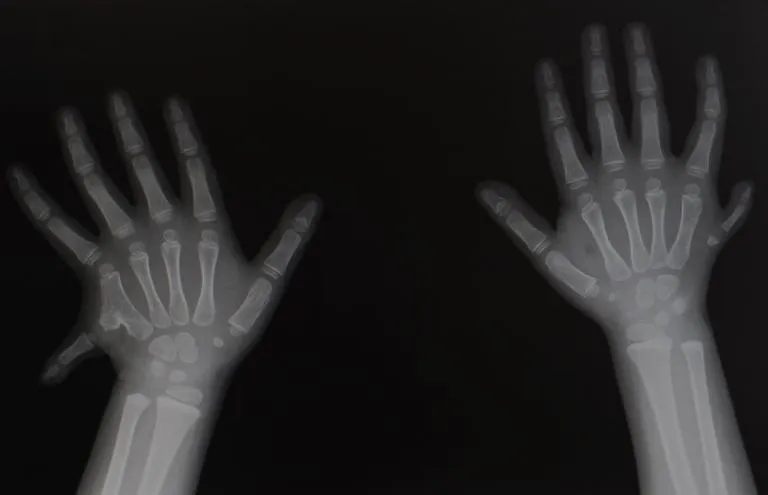

Polydactyly is the condition where a baby is born with extra fingers or toes. This issue tends to run in families. It may also result from genetic mutations or environmental causes. The usual treatment is surgery to remove the extra digit.

Polydactyly is the medical term for being born with extra fingers or toes. It’s one of the most common birth defects that affects babies’ hands and feet. The treatment of polydactyly depends on the location of your child’s extra finger or toe.

Polydactyly is clarified by the location the extra digit is located, these types include:

Preaxial (radial/tibial) polydactyly: An extra thumb or big toe.

Central polydactyly: An extra finger or toe near the middle digits (between the index, middle, or ring fingers or any of the toes that aren’t the big or pinkie toe).

Postaxial (ulnar/fibular) polydactyly: An extra pinkie finger or toe.